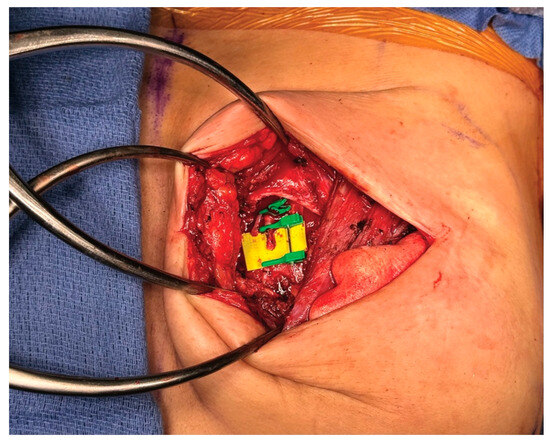

3.4. Operative Technique

4.4. Operative Technique